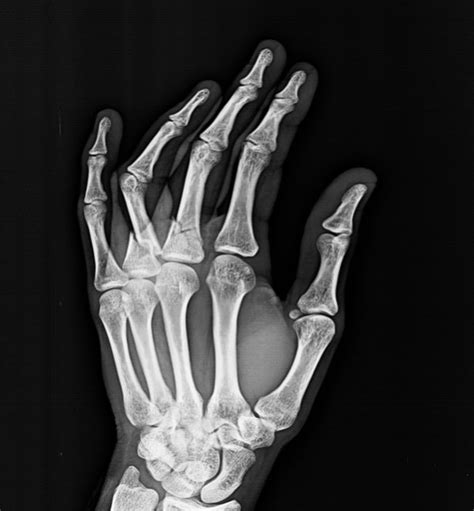

Left phalanx fracture icd 10all software. Distal phalanx is most common fractured bone in the hand.

You can always come back for icd 10 code for middle phalanx fracture because we update all the latest coupons and special deals weekly. Richards talks about distal phalanx fracture. Most common injuries to the skeletal system. Fracture of unsp phalanx of unsp finger, init for clos fx. They often result from direct trauma crush injuries to the distal phalanx are also common and can result in nail trauma and open fractures. To code a diagnosis of this type, you must use one of the six child codes of s62.51 that describes the diagnosis 'fracture of proximal phalanx of thumb' in more detail. Distal phalanx is most common fractured bone in the hand. Below are 48 working coupons for icd 10 code for middle phalanx fracture from reliable websites that we have updated for users to get maximum savings. Cureus phalangeal fracture secondary to hammering one's finger. It became clear, however, that the traditional. Left phalanx fracture icd 10all software. Overview of fractures in the pediatric age group. The fracture description above is well defined and includes description that supports the necessary items such as traumatic, open, displaced, middle of femur shaft, subsequent encounter. Account for 10% of all fractures. › verified 14 days ago. You can always come back for icd 10 code for middle phalanx fracture because we update all the latest coupons and special deals weekly. Macrocephaly mandibulofacial dysostosis treacher collins syndrome oculomandibular dysostosis other specified congenital malformations of skull and maxillary fracture, unspecified, initial encounter for open fracture fracture of zygoma bones, unspecified, initial.